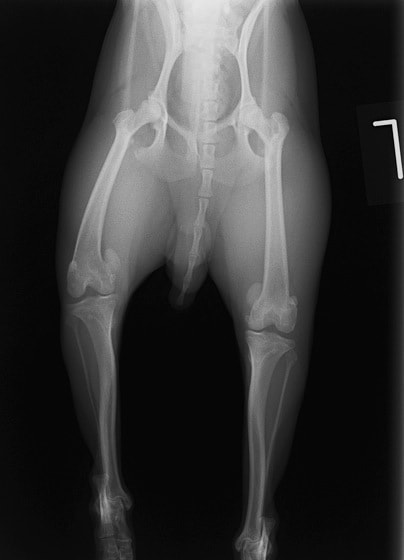

■ 症例24 キャバリア 7か月

左右膝蓋骨内方脱臼(左:グレードⅣ 右:グレードⅢ)

以前から左右後肢の跛行が認められ、整形外科学的検査・レントゲン検査により左右の膝蓋骨脱臼が認められた。症状が重度である左膝の膝蓋骨脱臼整復術を行った。外科手技は縫工筋及び内側広筋の解放、脛骨粗面の外側転位、滑車ブロック形造溝術、内外側関節方の縫縮を実施した。術後一か月時点で、左の膝蓋骨は安定しており経過は良好である。

本症例は成長期における重度の膝蓋骨脱臼であり、術後の再発の可能性もあるため、経過をしっかりと観察していく必要がある。また、今回手術を実施していない右膝に関しても経過を観察し、手術を検討していくこととする。